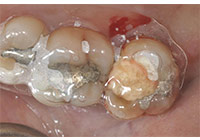

齲齒由口腔中多種因素復合作用所導致的牙齒硬組織進行性病損,表現為無機質脫礦和有機質分解,隨病程發展而從色澤改變到形成實質性病損的演變過程。齲齒是細菌性疾病,因此它可以繼發牙髓炎和根尖周炎,甚至能引起牙槽骨和頜骨炎癥。(圖01~04)

圖3

圖4